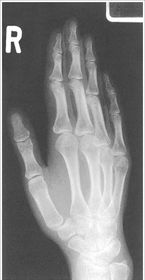

| PA Hand | distal phalynxes are bent flatten hand to true PA *should be equal concavity on all digits* |

| PA Hand | obliqued - fingers are not equally concave on both sides distal metacarpals are overlapped |

| PA Hand | ANATOMY: entire hand including 1'' of distal radius and ulna CRITERIA: equal concavity on either side of digits digits separated with no superimposition open joint spaces POSITIONING: CR perpendicular @ 3rd MCP joint |